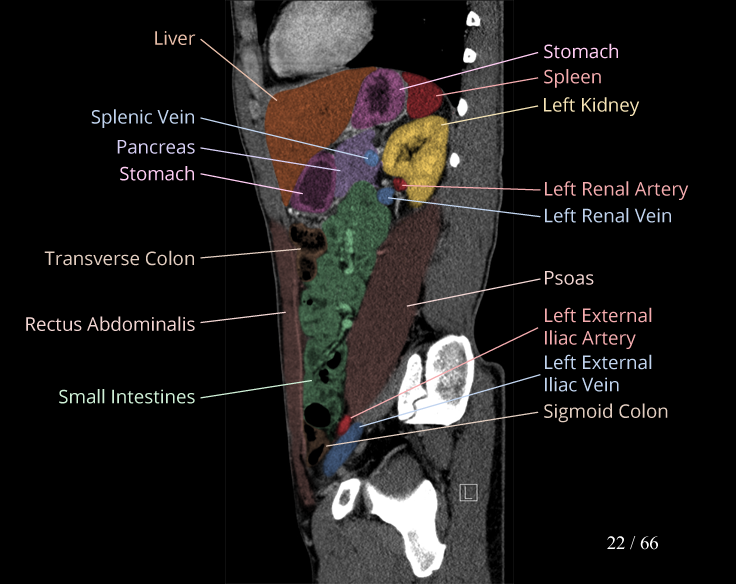

Body

Covers abdominal CT anatomy.